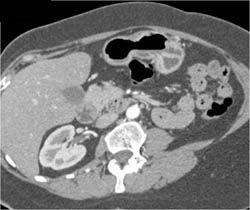

Diagnosis

Multiple Vascular Tumors in Duodenum and Stomachmultiple Vascular Tumors in Duodenum and Stomach